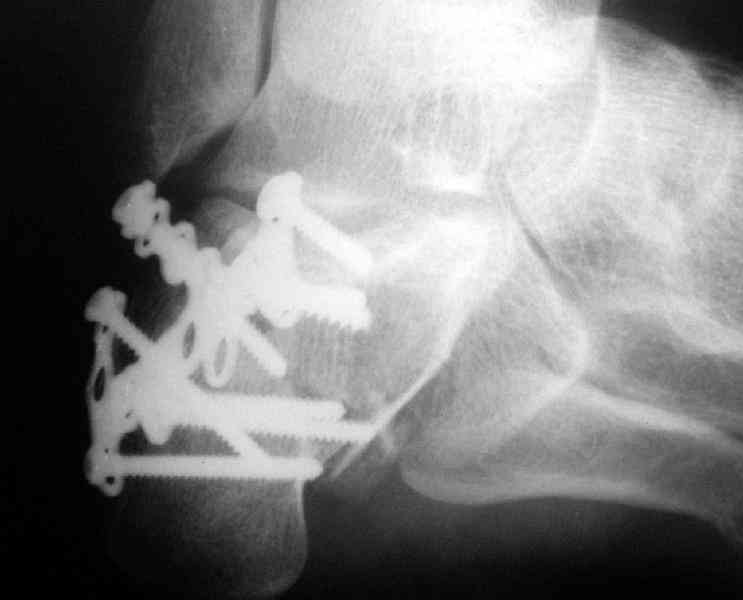

Re: Перелом пяточной кости

Пяточной пластиной

Открытый и закрытый способы лечения.